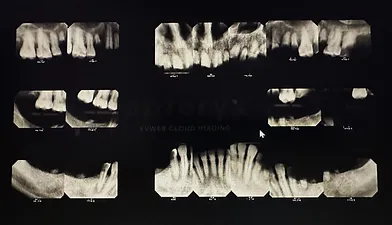

The Following pictures show case a patient that needed extraction of all his teeth in order to have a dental clearance for his knee replacement surgery.